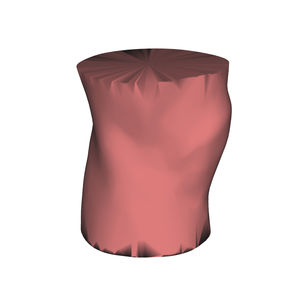

Anatomisches Modell / Schulter HUM-Efür Punktionenfür Injektionenfür Ultraschalluntersuchungen

- Körperteil

- Schulter

- Farbe

- rosa

Echogene und röntgendichte anatomische Schaufensterpuppen

für eine bessere Ausbildung in interventionellen Verfahren unter Ultraschall und Röntgenstrahlen

Identifizierung anatomischer Orientierungspunkte mit Ultraschall und Röntgenstrahlen

Training für Punktion und Infiltration unter Ultraschall und Röntgenstrahlen

Hautgetreues Stichempfinden mittels Echo und Radio

Alle unsere Schaufensterpuppen sind echogen und röntgendicht und können bis zu 600 Injektionen pro Stelle tragen.